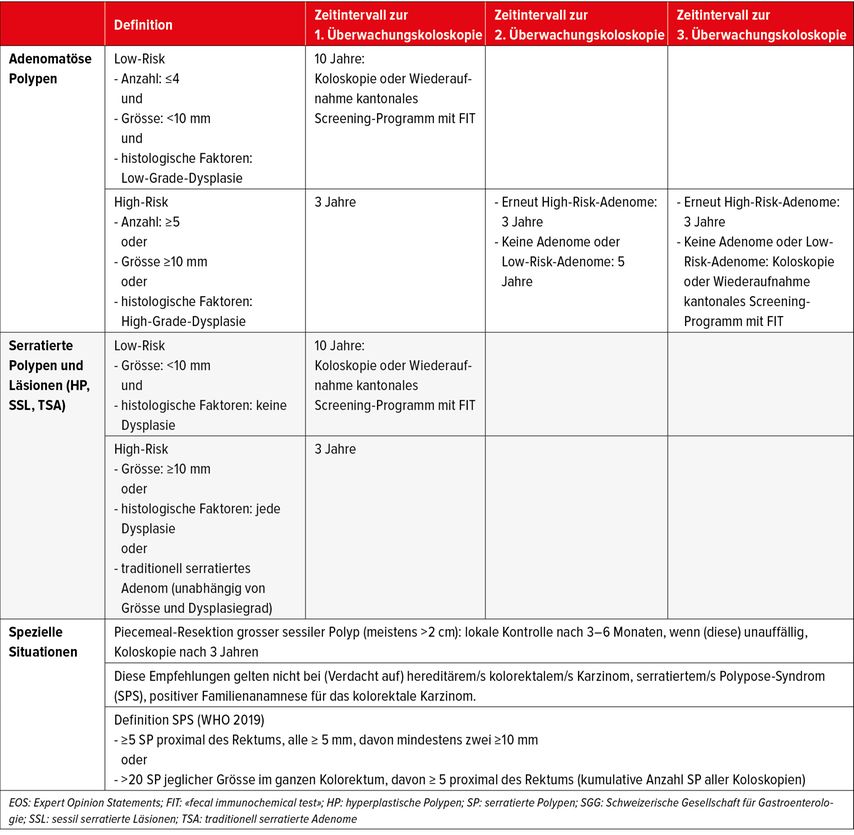

Die klinische Relevanz einer gesteigerten Polypendetektionsrate liegt in der korrekten Wahl des Polypennachsorgeintervalls. Diesbezüglich wurden 2022 in der Schweiz von der nationalen Fachgesellschaft neue Nachsorgeempfehlungen publiziert.7 Grundsätzlich wird in dem Schema zwischen adenomatösen Polypen und sessilen serratierten Läsionen unterschieden, da sie sich in ihrer Karzinogenese unterscheiden. Es werden jeweils Situationen mit geringerem von solchen mit hohem Risiko unterschieden (Tab. 1).

Tab. 1: Konsensus-Empfehlungen zur Nachsorge nach koloskopischer Polypektomie. Voraussetzung: vgl. EOS, SGG-Wegleitung Koloskopie/Screening-Koloskopie (aus Truninger et al.: Swiss Med Forum 2022; 22: 349-55, published under the copyright license CC BY-NC-ND 4.0)7

Bei geringem Risiko (≤4 Adenome jeweils <10mm) wird eine Surveillance-Koloskopie nach 10 Jahren empfohlen, sofern keine höhergradige Dysplasie vorliegt. Bei allen anderen Adenomen wird eine Nachsorgekoloskopie bereits nach 3 Jahren empfohlen. Wenn zu diesem Zeitpunkt eine Situation mit geringem Risiko vorliegt, erfolgt die nächste Surveillance-Koloskopie in 5 Jahren und dann nach dem üblichen Schema. Bei sessilen serratierten Polypen oder Läsionen8 <10mm und ohne Nachweis einer Dysplasie ist ebenfalls erst in 10 Jahren wieder eine Surveillance-Koloskopie zu planen, wohingegen bei höherem Risiko (Polypen von ≥10mm mit jedem Dysplasiegrad oder traditionell serratierten Adenomen unabhängig von Grösse und Dysplasiegrad) eine Surveillance-Koloskopie in 3 Jahren zu empfohlen wird. Die Verlängerung des bisherigen Nachsorgeintervalls von 5 auf 10 Jahre hat unter Ärzten und auch unter den Patienten, die diese Intervalle zum Teil über Jahre gewohnt waren, eine gewisse Unruhe ausgelöst, ist im Hinblick auf ein individualisiertes Vorgehen je nach Risiko aber berechtigt. In dem Zusammenhang ist zu beachten, dass diese allgemeinen Empfehlungen in speziellen Situationen jedoch nicht gelten, beispielsweise nach fraktionierter («piece-meal»-) Resektion grosser sessiler Polypen >2cm, bei positiver Familienanamnese für das kolorektale Karzinom, hereditäre kolorektale Karzinome oder serratierte Polyposissyndrome, definiert als >5 serratierte Polypen proximal des Rektums, alle >5mm, mindestens 2 davon >10mm oder >20 serratierte Läsionen jeglicher Grösse, davon mindestens 5 oberhalb des Rektums (Tab. 1).7